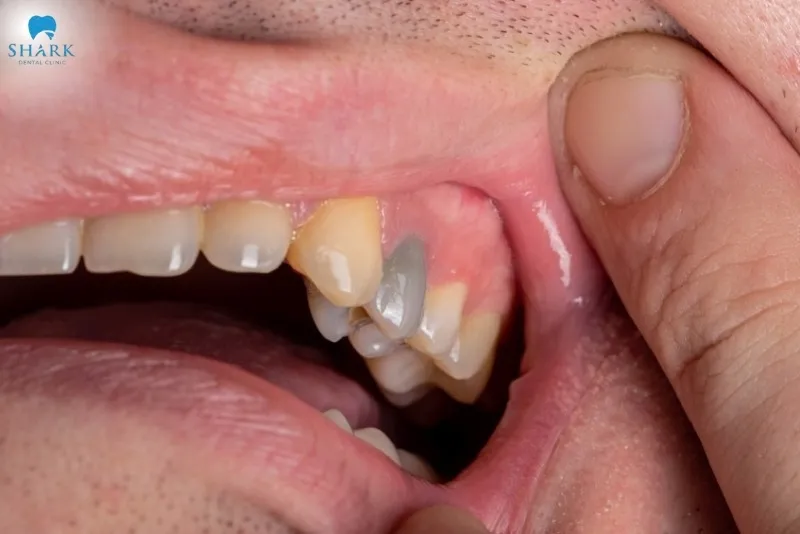

- Gradual color change in the dead tooth to gray, dark yellow-brown, or black due to the degeneration of substances within the root canal.

- Pus-filled bumps or abscesses appearing around the area of the necrotic tooth.

- Swelling of the gums, cheeks, or infection surrounding the dead tooth.